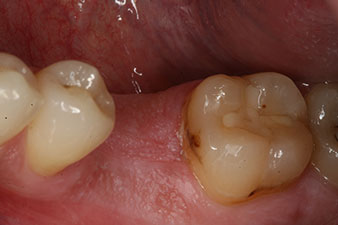

impression

Fig. 8: The impression for the final crown is taken.

Therefore, successful osseointegration and adequate biological stability could be recorded, which enabled an impression to be taken in the same session.

The final pictures show the screw-retained monolithic composite crown in place and the x-ray check (Fig. 9 and 10) (6).